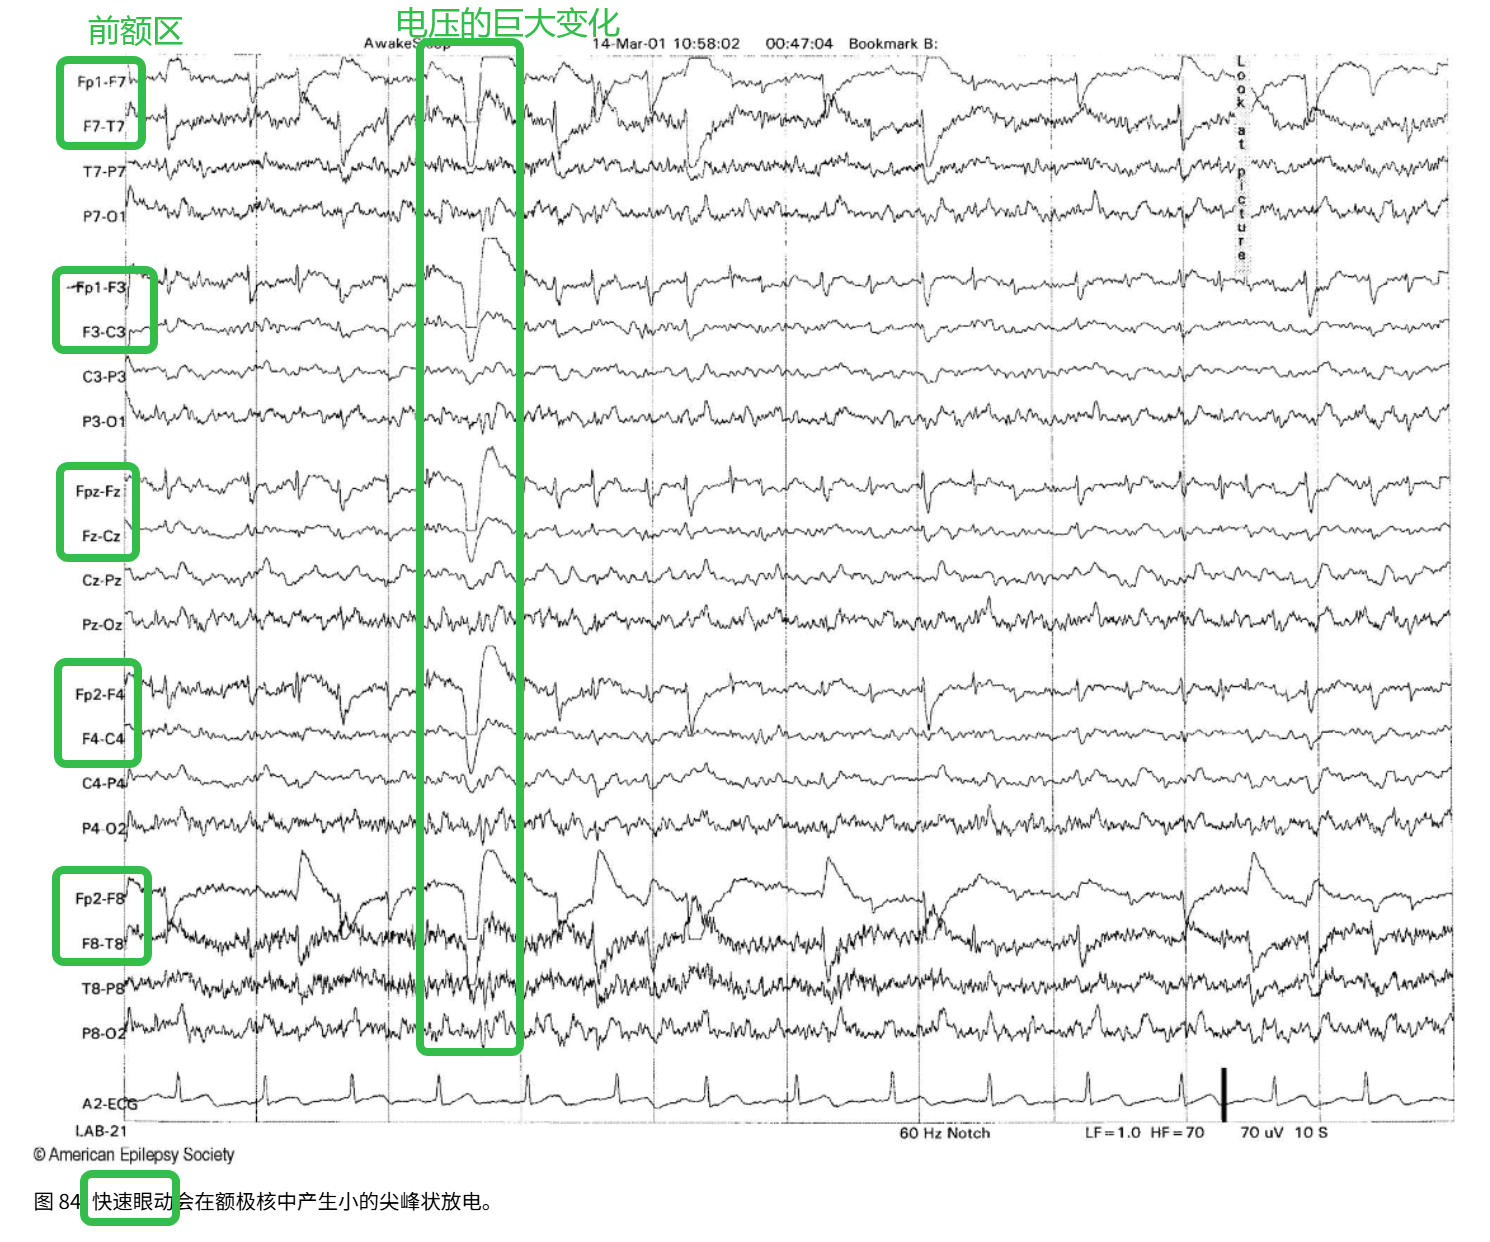

(2)快速眼动

特征:显著的眼动电位变化

波型:β波,眨眼时波幅高、持续时间短

区域:前额区明显

在这里插入图片描述